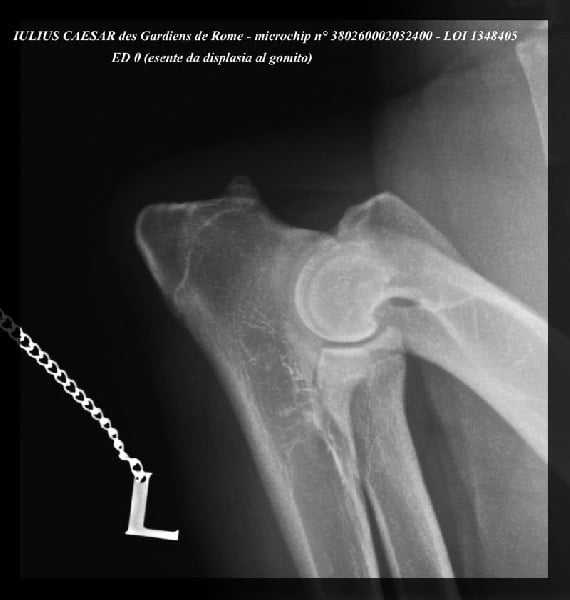

| Puce | 380260002032400 |

| N° origine | LOI 1348405 |